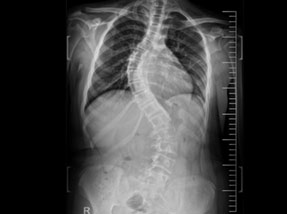

• Pre-Surgery

Case 1